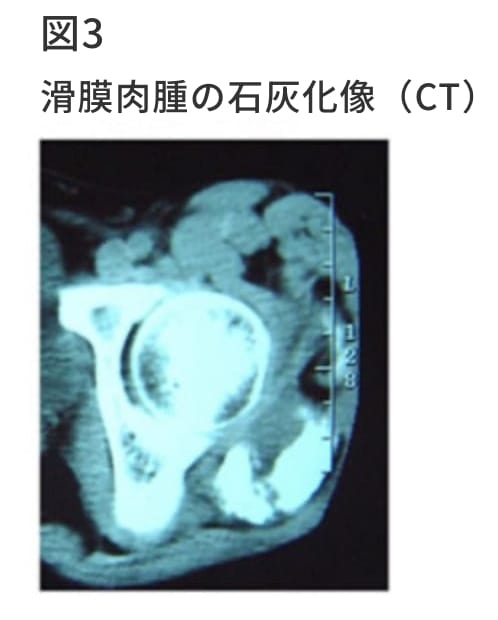

近年MRIをはじめとして様々な画像診断が登場してきたが、骨腫瘍の診断では単純レントゲン写真の診断的価値は、少しも失われていない。腫瘍の占拠部位とその広がり、骨破壊の程度などを読みとる。骨腫瘍の中には非常に特徴的なレントゲン像を示すので、病理診断を待たずして診断を下しうる腫瘍も少なくない。特に骨腫瘍の場合その発生部位は、おおよそ決まっており診断する上で重要な情報源となる。単純レントゲン写真は軟部腫瘍の診断の際にも、最初に行うべき検査である。血管腫、滑膜肉腫、骨外性骨肉腫のように石灰化または骨化を伴う腫瘍を診断するためにはレントゲン写真は最も簡便な検査といえる。またレントゲン上の腫瘍陰影から、そのサイズ、骨との関係を簡便に知ることが出来る。また骨軟部腫瘍で臨床的に悪性腫瘍を疑う際には胸部レントゲンを撮影し、原発巣、肺転移巣の有無をスクリーニングする必要がある。

骨腫瘍においては、CTスキャンは骨腫瘍の病変部の石灰化または骨化の有無、皮質骨の破壊の程度、海綿骨の骨破壊の状態、微細な骨膜反応、病巣の辺縁の骨硬化の状態など単純X線やMRIでは十分に描出できない骨変化を知るのに適している。また軟部腫瘍においては腫瘍内部の石灰化または骨化を知るのに非常に有用である。